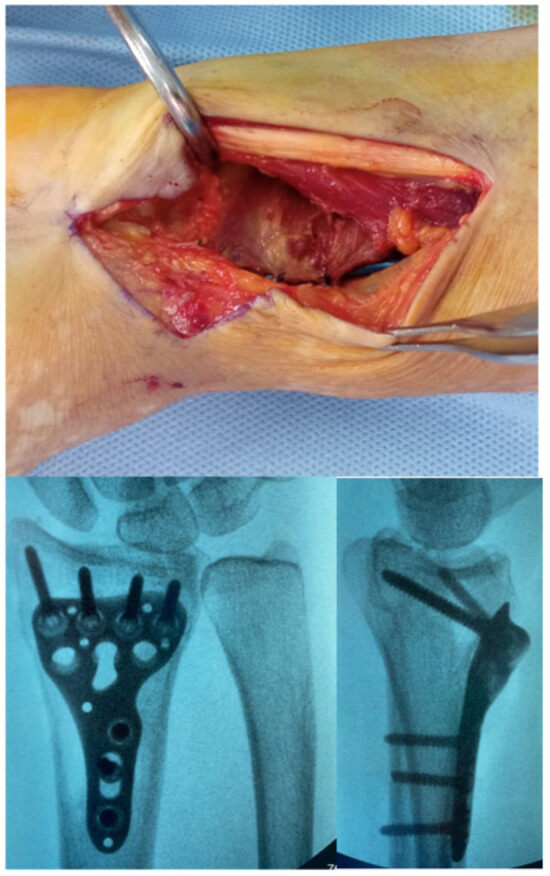

The volar plate is then positioned according to standard variable-angle principles. Additional fixation of the radial styloid may be achieved using one or two 3.0 mm headless screws inserted percutaneously or, alternatively, with a dedicated radial styloid plate. The pronator quadratus is then re-approximated to cover the plate, minimizing the risk of flexor pollicis longus irritation. Final fluoroscopic images are obtained to confirm reduction and hardware placement (Figure 6).

Figure 6. Final closure of the Pronator Quadratus and post operative X-ray control.

Surgeries 06 00104 g006